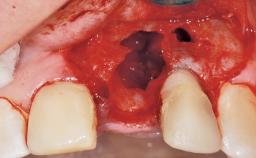

Immediate Flapless Placement of an Implant in a Maxillary Left Central Incisor Site

A 29-year-old female patient presented for treatment to replace the upper left central incisor tooth with an implant- supported restoration. The tooth had been intermittently symptomatic for the previous 12 months. The tooth had originally suffered trauma about 15 years previously. Several endodontic treatments had been performed, including an apicectomy procedure to retain the tooth. The patient was healthy and a non-smoker. She had reasonable expectations in regard to esthetic outcomes and the risk of marginal tissue recession following treatment. At medium smile, the gingival margins of the upper teeth were visible, with a display of 3 to 4 mm of the gingival margins. Gingival recession of tooth 21 and a discrepancy in the gingival levels between teeth 11 and 21 was observable during normal speech and smile.

| Socket Integrity | Damage to one or more bone walls |

| Bone Volume | Damage to one or more socket walls |